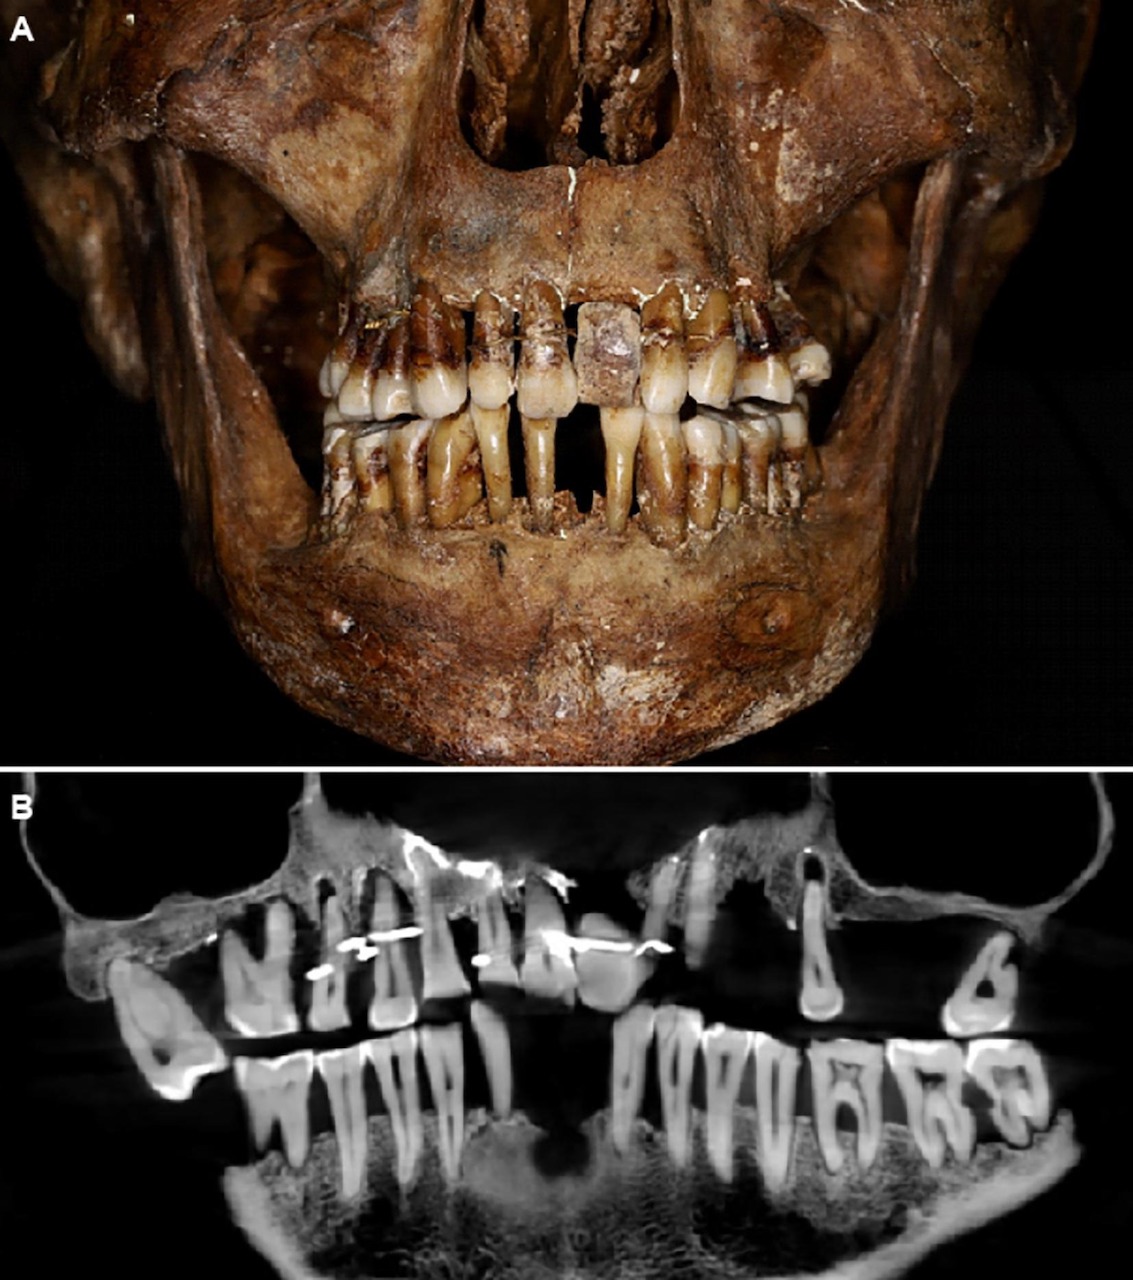

In 1988 werd het skelet van deze edelvrouw ontdekt tijdens opgravingen in Noordwest-Frankrijk. Het lichaam van Anne was gebalsemd en lag in een loden kist. Hierdoor is het skelet goed bewaard gebleven. Toen al zagen de archeologen dat er iets vreemds was met haar gebit maar er werd pas kortgeleden meer onderzoek naar gedaan door de Franse archeoloog Rozenn Colleter. Er werden röntgenscans van de schedel gemaakt en een digitaal 3D model van haar gebit. Men zag dat Anne parodontitis had, dat is ernstige tandvleesontsteking met verlies van tanden en kaakbot tot gevolg. Haar tanden bleken bijeengehouden met gouddraad wat om de tandhalzen was gewikkeld, vlak bij het tandvlees. Deze gouden ‘spalkjes’ hielden de tanden op zijn plaats. Op de plek van een uitgevallen tand was een kunsttand gemaakt uit de slagtand van een olifant. Ook deze kunsttand werd met een gouden ‘spalkje’ op zijn plek gehouden.

Voor die tijd zeer vooruitstrevend en zeker ook zeer pijnlijk. Het hebben van parodontitis is al geen pretje en met draadjes om blootliggende tandhalzen of zelfs door een tand heen moet het wel heel pijnlijk voor deze edelvrouw zijn geweest. Ook eten met zo’n bijeengehouden gebit zal bijna onmogelijk zijn geweest. Huidige inzichten laten zien dat deze methode met gouden spalkjes het gebit nog verder verzwakte. Of de reden cosmetisch was of toch een poging om het gebit te behouden, het maakt niet uit. Het blijft heel bijzonder hoe in die tijd hoe is geprobeerd een oplossing te vinden voor de gevolgen van parodontitis.